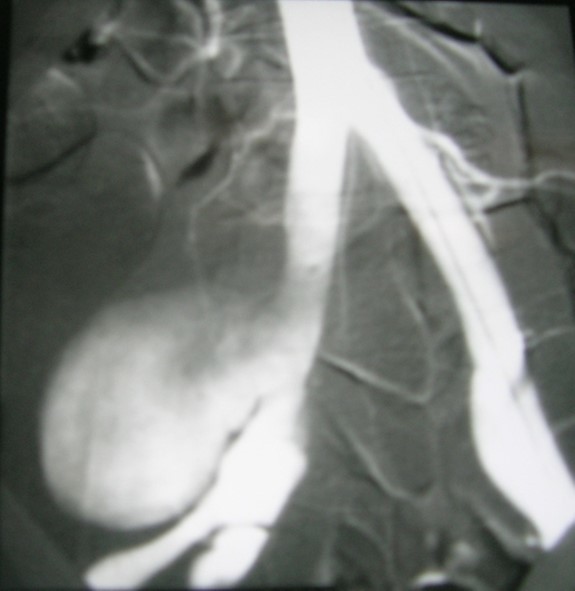

A45-year-old man, with no prior pathologic antecedent was admitted to the internal medicine department for a 3weeks history of abdominal pain. This symptom occurred in the context of apyrexia and 4 kilogram weight loss. Abdominal examination was a painful abdomen, distended. The skin examination noted painful genital andoral ulcers with pustlar lesions in the back. Angio CT scan revealed an aneurysm of the right common iliac artery (Figure 1).Artégraphie the lesion showed the same described above, showing the saccular aneurysm (Figure 2). He had no other aneurysmal localizations.

Figure 2.Artégraphie showed the saccular aneurysm.